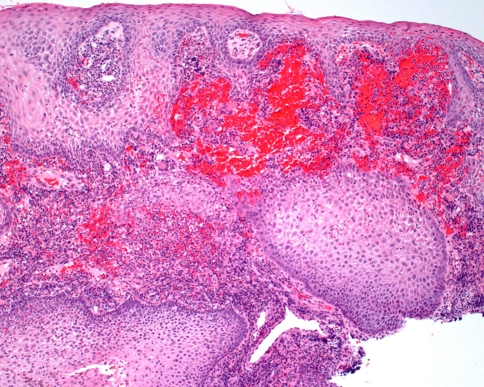

Because significant inflammation is such a common finding in many gingival specimens, the possibility of Wegener’s granulomatosis can be easily overlooked. However, the combination of several features is highly suggestive of the diagnosis. First, there is prominent hemorrhage in the superficial connective tissue, which corresponds to the petechial appearance observed clinically (Fig. 9). Second, the overlying epithelium often demonstrates striking pseudoepitheliomatous hyperplasia. A heavy inflammatory infiltrate is present, which includes numerous eosinophils and scattered multinucleated giant cells (Fig. 10). Neutrophilic abscesses sometimes are seen within the epithelium. Because few large blood vessels are present within the gingiva, it may be difficult to demonstrate the presence of classic vasculitis.

Fig. 9.

Wegener’s granulomatosis. This low power photomicrograph from a gingival lesion demonstrates pseudoepitheliomatous hyperplasia of the epithelium with prominent subepithelial hemorrhage